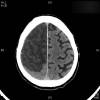

Atrofia cortico-subcortical de predominio frontotemporal.